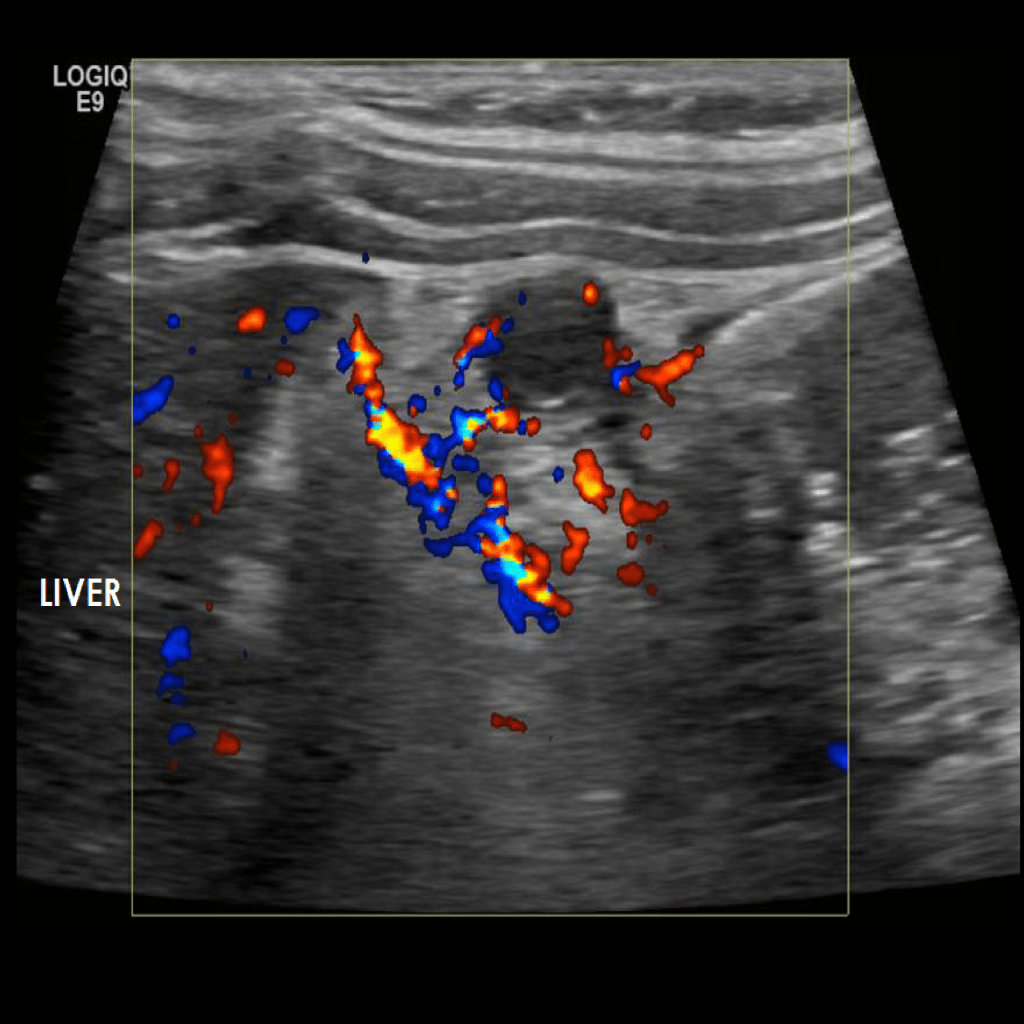

Appendicitis 10

1 cm Appendicitis located subhepatically.